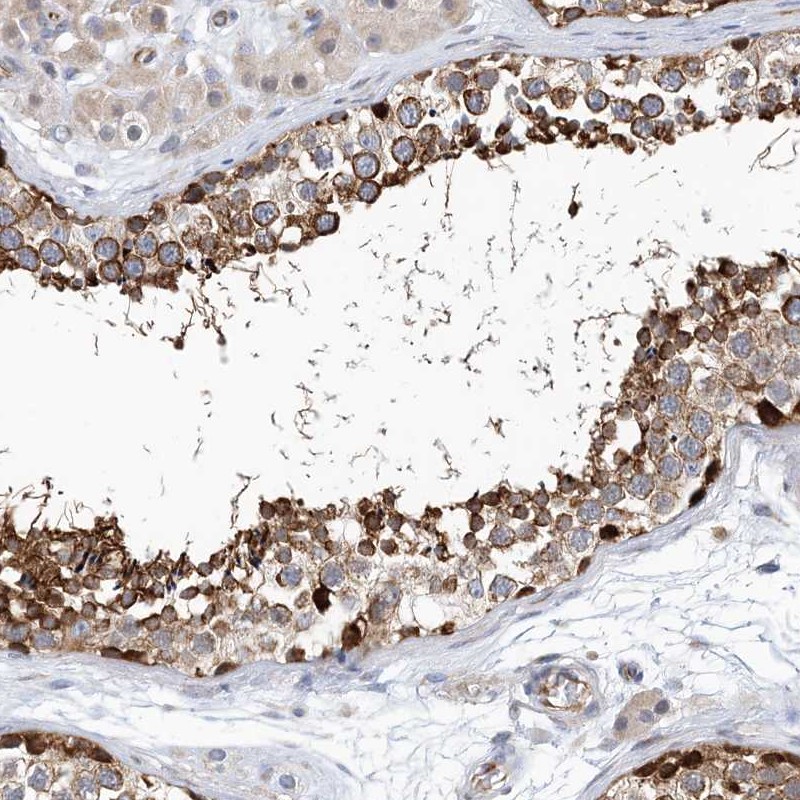

Immunohistochemical staining of human testis shows strong cytoplasmic positivity in cells in seminiferus ducts.